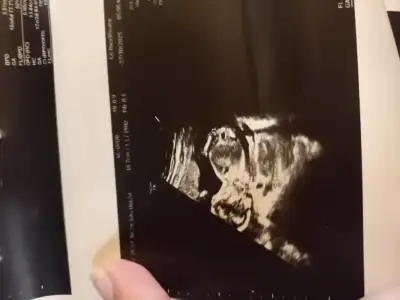

Kiz sankiKizlaar bugün cinsiyeti öğrendik ama parti Cumartesi günü ve meraktan çatlıyorum tahmini olan var miiii

Ay benim bir tahminim yok ama hayırlı olsunn. Daha da çok varmış cumartesiyeee. Biz de öğrendiğimiz günün ertesi gününe hemen parti organize etmiştik çatlardık yoksa hahahahKizlaar bugün cinsiyeti öğrendik ama parti Cumartesi günü ve meraktan çatlıyorum tahmini olan var miiii

Ay yukarı doğru bir şey görüyor gibi oluyorum doktor da ben anlamayim diye tam ultrason görüntüleri vermediKiz sanki

Bende tam secemedim acikcasiAy yukarı doğru bir şey görüyor gibi oluyorum doktor da ben anlamayim diye tam ultrason görüntüleri vermedi

Hatta bakarken dedim ne bicim cekmis resmen anlasilmasin diye

Bana da erkek diyorduYapay zeka erkek diyor

Hatta ben dedim ki nasil erkek? Cikinti var mi ki? Nubu duz gibi?

Aa evet yakaladin beni nubu duz o zaman kiz bu kesinnnnnn

Sende yaz bak

Hani nerde cikinti nubu duz falan yaz hemen R yapiyor

Aaaaa dur yapayım hemenBana da erkek diyordu

Hatta ben dedim ki nasil erkek? Cikinti var mi ki? Nubu duz gibi?

Aa evet yakaladin beni nubu duz o zaman kiz bu kesinnnnnnfalan demisti donek

Sende yaz bak

Hani nerde cikinti nubu duz falan yaz hemen R yapiyor

Haahahahah bende duramıyorum sırf ben bakarım diye zimbaladi ve kötü görüntü verdi doktorBende tam secemedim acikcasi

Hatta bakarken dedim ne bicim cekmis resmen anlasilmasin diye

Ben hic parti insani degilim ya o zarfta yazarken uyuyamam acar bakarim sonra salak yaparim yeni ogrenmis gibi sfjdjf